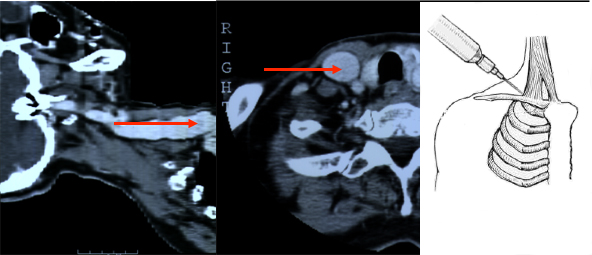

Von links eingeführte Katheter stoßen in der in mehreren Ebenen gewundenen Vena brachiocephalica an die Venenwand an und verursachen Intimaläsionen und Thrombosen. Die Wandschäden sind umso schlimmer, je steifer der Katheter ist. Die schlimmsten Schäden rufen die in der Intensivmedizin üblichen lage bore Katheter hervor.

Etwa 10% der Bevölkerung haben als embryologisch bedingte Anomalie eine links persistierende obere Hohlvene, die meist in den Sinus coronarius mündet. Liegt ein von links eingebrachter Katheter im Sinus coronarius, dem venösen Abfluß des Herzens, kann die Infusion hochosmolarer Ernährungslösungen oder irritierender Zytostatika zu einer akuten Sinusthrombose mit Behinderung des venösen Abflusses aus dem Myokard führen. Der Anstieg des myokardialen Perfusionsdruckes führt zu einer Ischämie auch bei gesunden Koronararterien mit Infarkten, Arrhythmien und plötzlichem Herztod (W Masood, KK Sitammagari: Coronary Sinus Thrombosis. StatPearls Publishing; 2020 ).

Um die Vena subclavia zu punktieren, muß horizontal unter der Clavicula in Richtung Manubrium sterni eingestochen werden. Dies gelingt nur, wenn der Patient auf einer harten Unterlage mit einem Hypomochlion unter der Wirbelsäule liegt, dass die Schultern nach hinten fallen.

Bei falscher Lagerung ohne Hypomochlion oder bei Punktion im Bett mit weicher Matratze führt die vorstehende Schulter zu schräger Punktion mit Verletzung der Lunge und Pneumothorax.

Bei älteren Patienten ist das Gewebe zwischen 1. Rippe und Clavicula oft sehr hart oder verknöchert. Wird dann zuviel Druck auf die Nadel ausgeübt, geht sie durch die Vene in die dahinter liegende A. carotis der Gegenseite mit der Folge eines Mediastinalhämatoms.